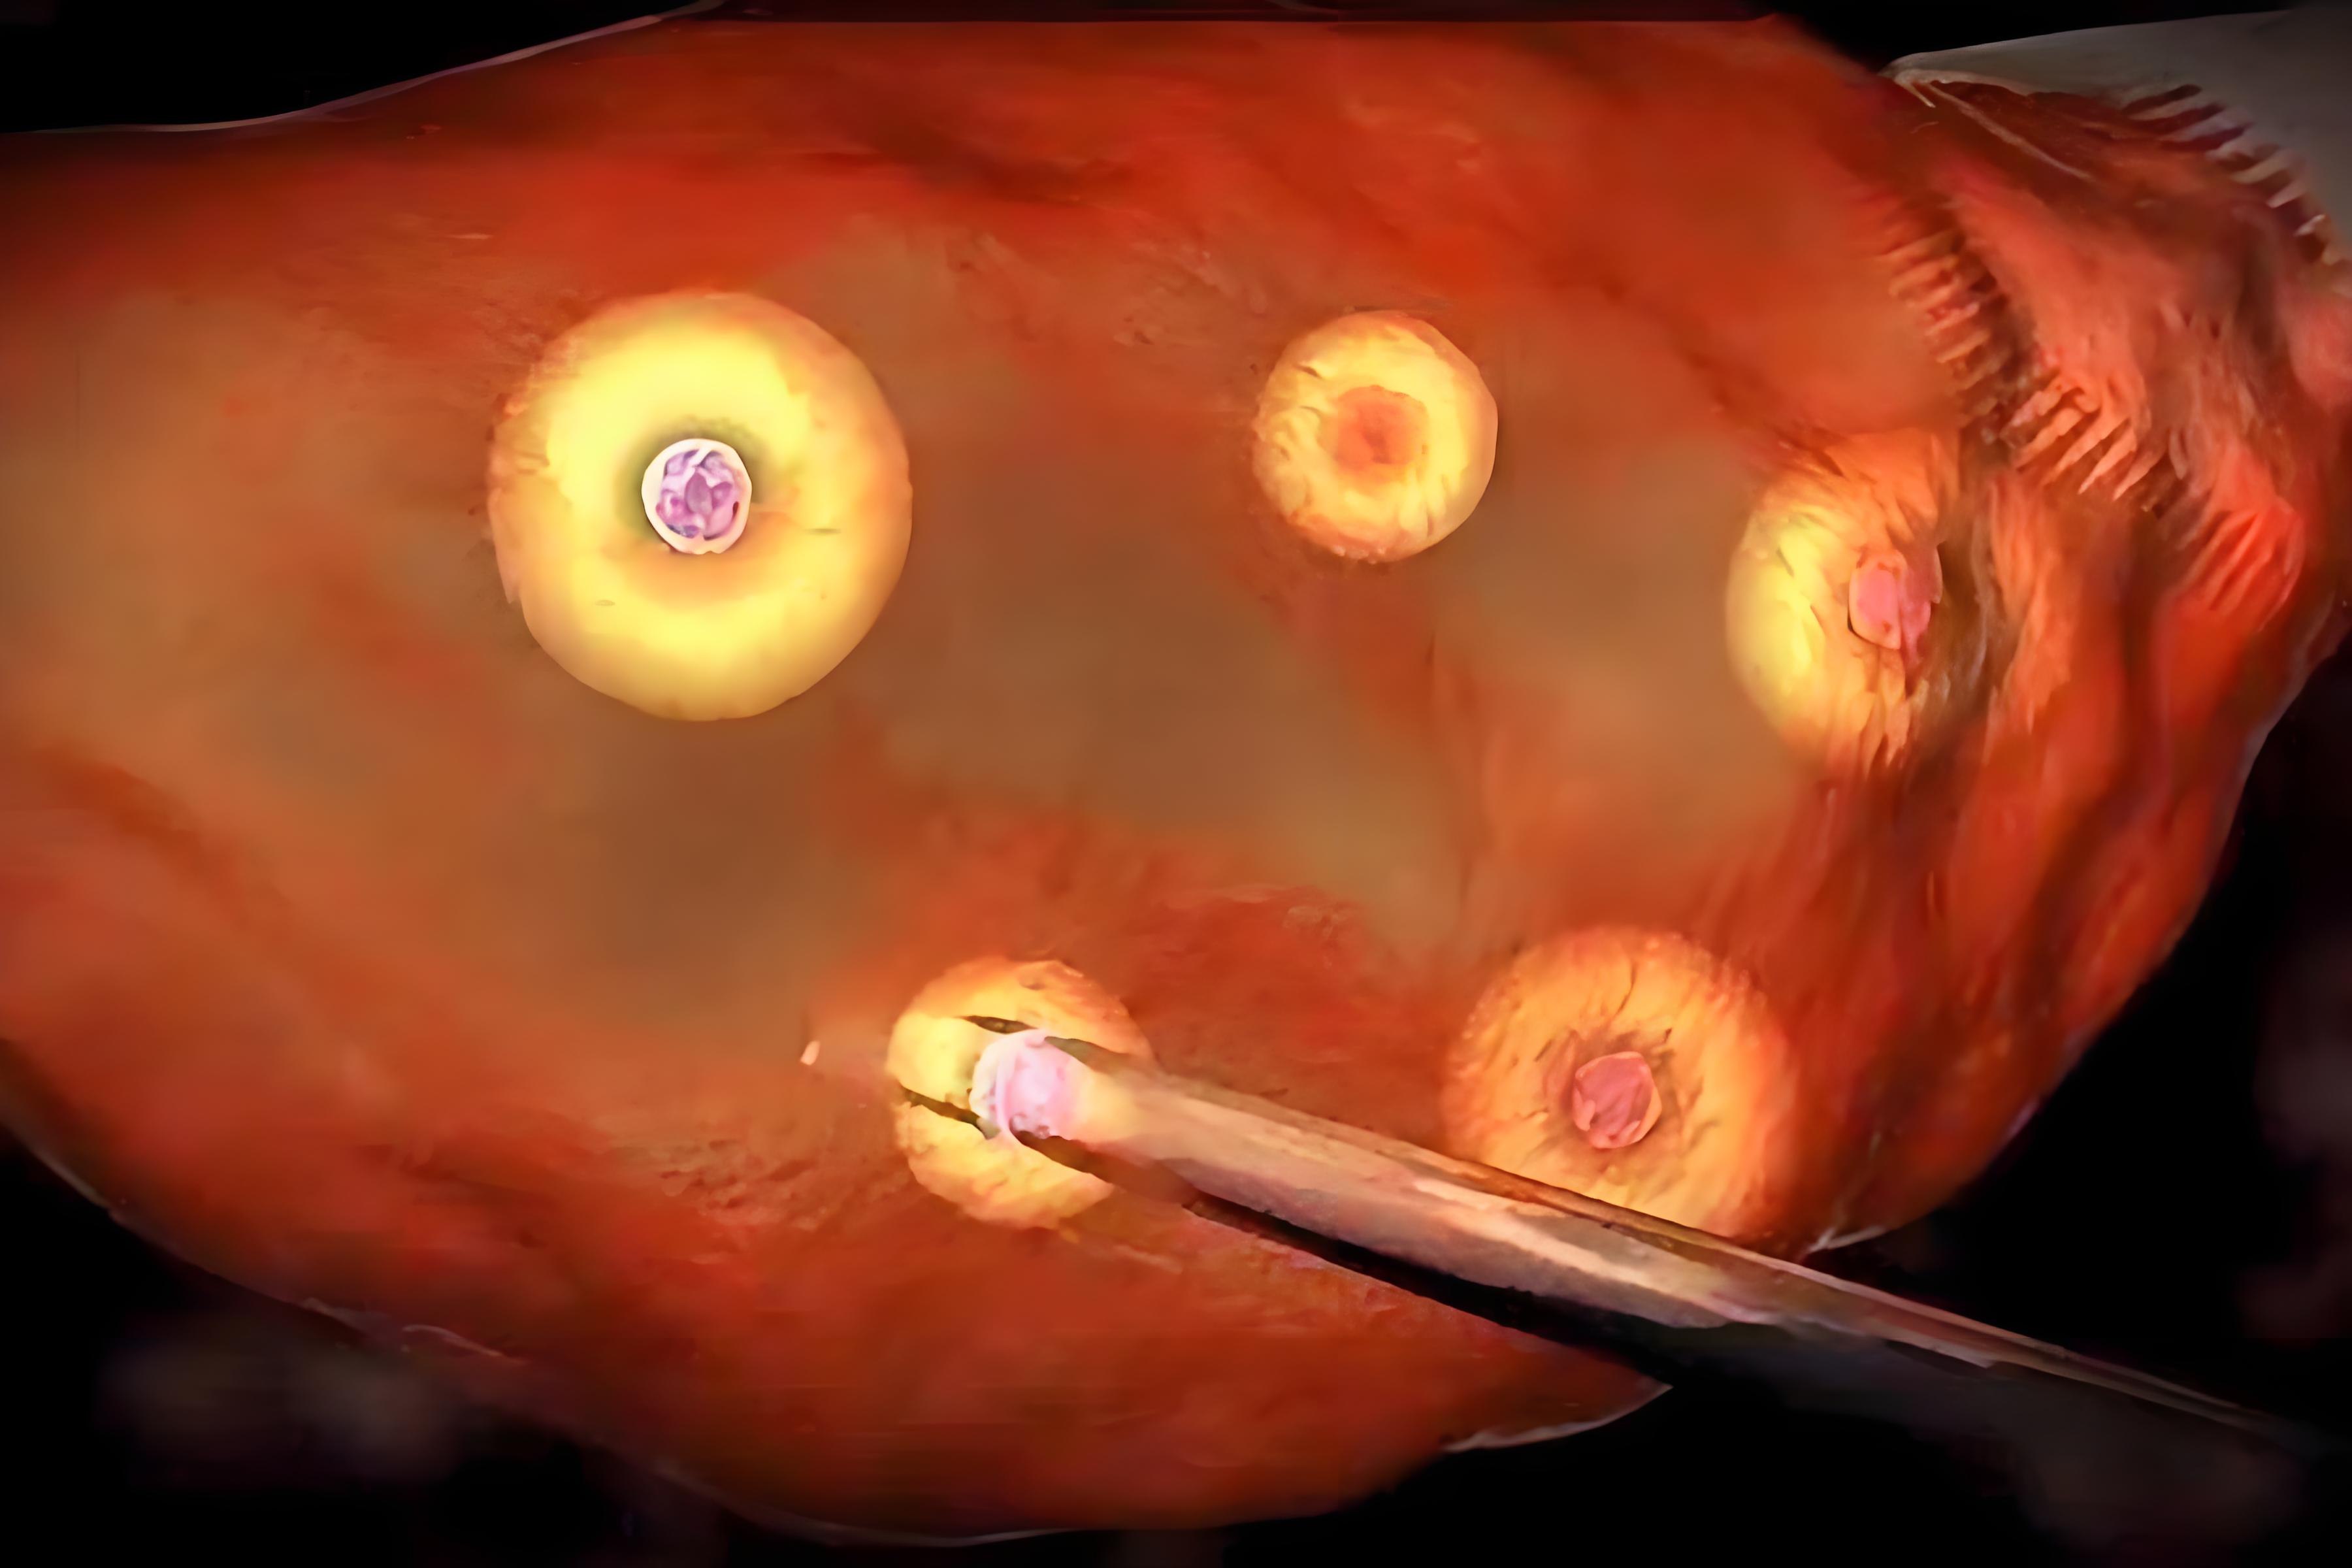

2、促排取卵

HRC专家会根据女性的生育年龄、卵巢功能、激素水平、卵泡储备量、身高体重等情况,为其量身定制合适的促排卵方案,并使用经美国FDA监管认证的天然、无副作用的药物进行促排。在女性用药过程中,专家会实时跟踪监测,以了解卵泡的发育情况,确定女性对促排卵药物的反应程度,并及时调整用药剂量和时长,有效规避腹水、多囊卵巢等并发症的发生,确保女性身体健康。之后专家会在卵泡发育成熟时进行取卵,以获得多个优质卵子。